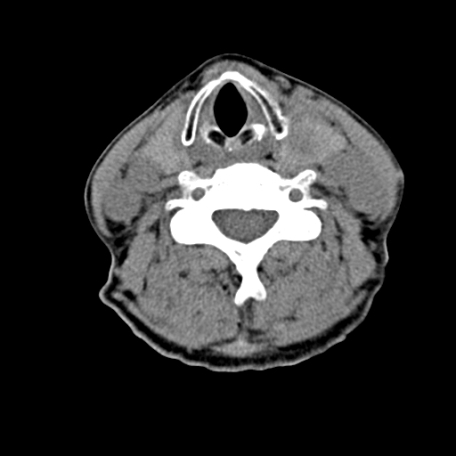

标题: CT24010:患者女56岁双侧甲状腺摘除术后一月复查,患者现感 [打印本页]

标题: CT24010:患者女56岁双侧甲状腺摘除术后一月复查,患者现感

甲状腺术后复发,现在甲状腺区域仍有密度不均匀之软组织密度影。

甲状腺区域密度不均匀密度影,应该是术后改变,要鉴别是否复发,建议增强检查。

“甲状腺摘除术后一月复查”,有病理吗?考虑术后复发,可能是恶性,颌下及左侧颈部淋巴结有肿大。

考虑术后复发,并颈部淋巴结肿大。请结合临床。

双侧甲状腺肿大,伴多发低密度灶(性质待定);建议行进一步检查。

双侧甲状腺肿大,周围结构不清,术后复发时间有点短,考虑出血并感染。